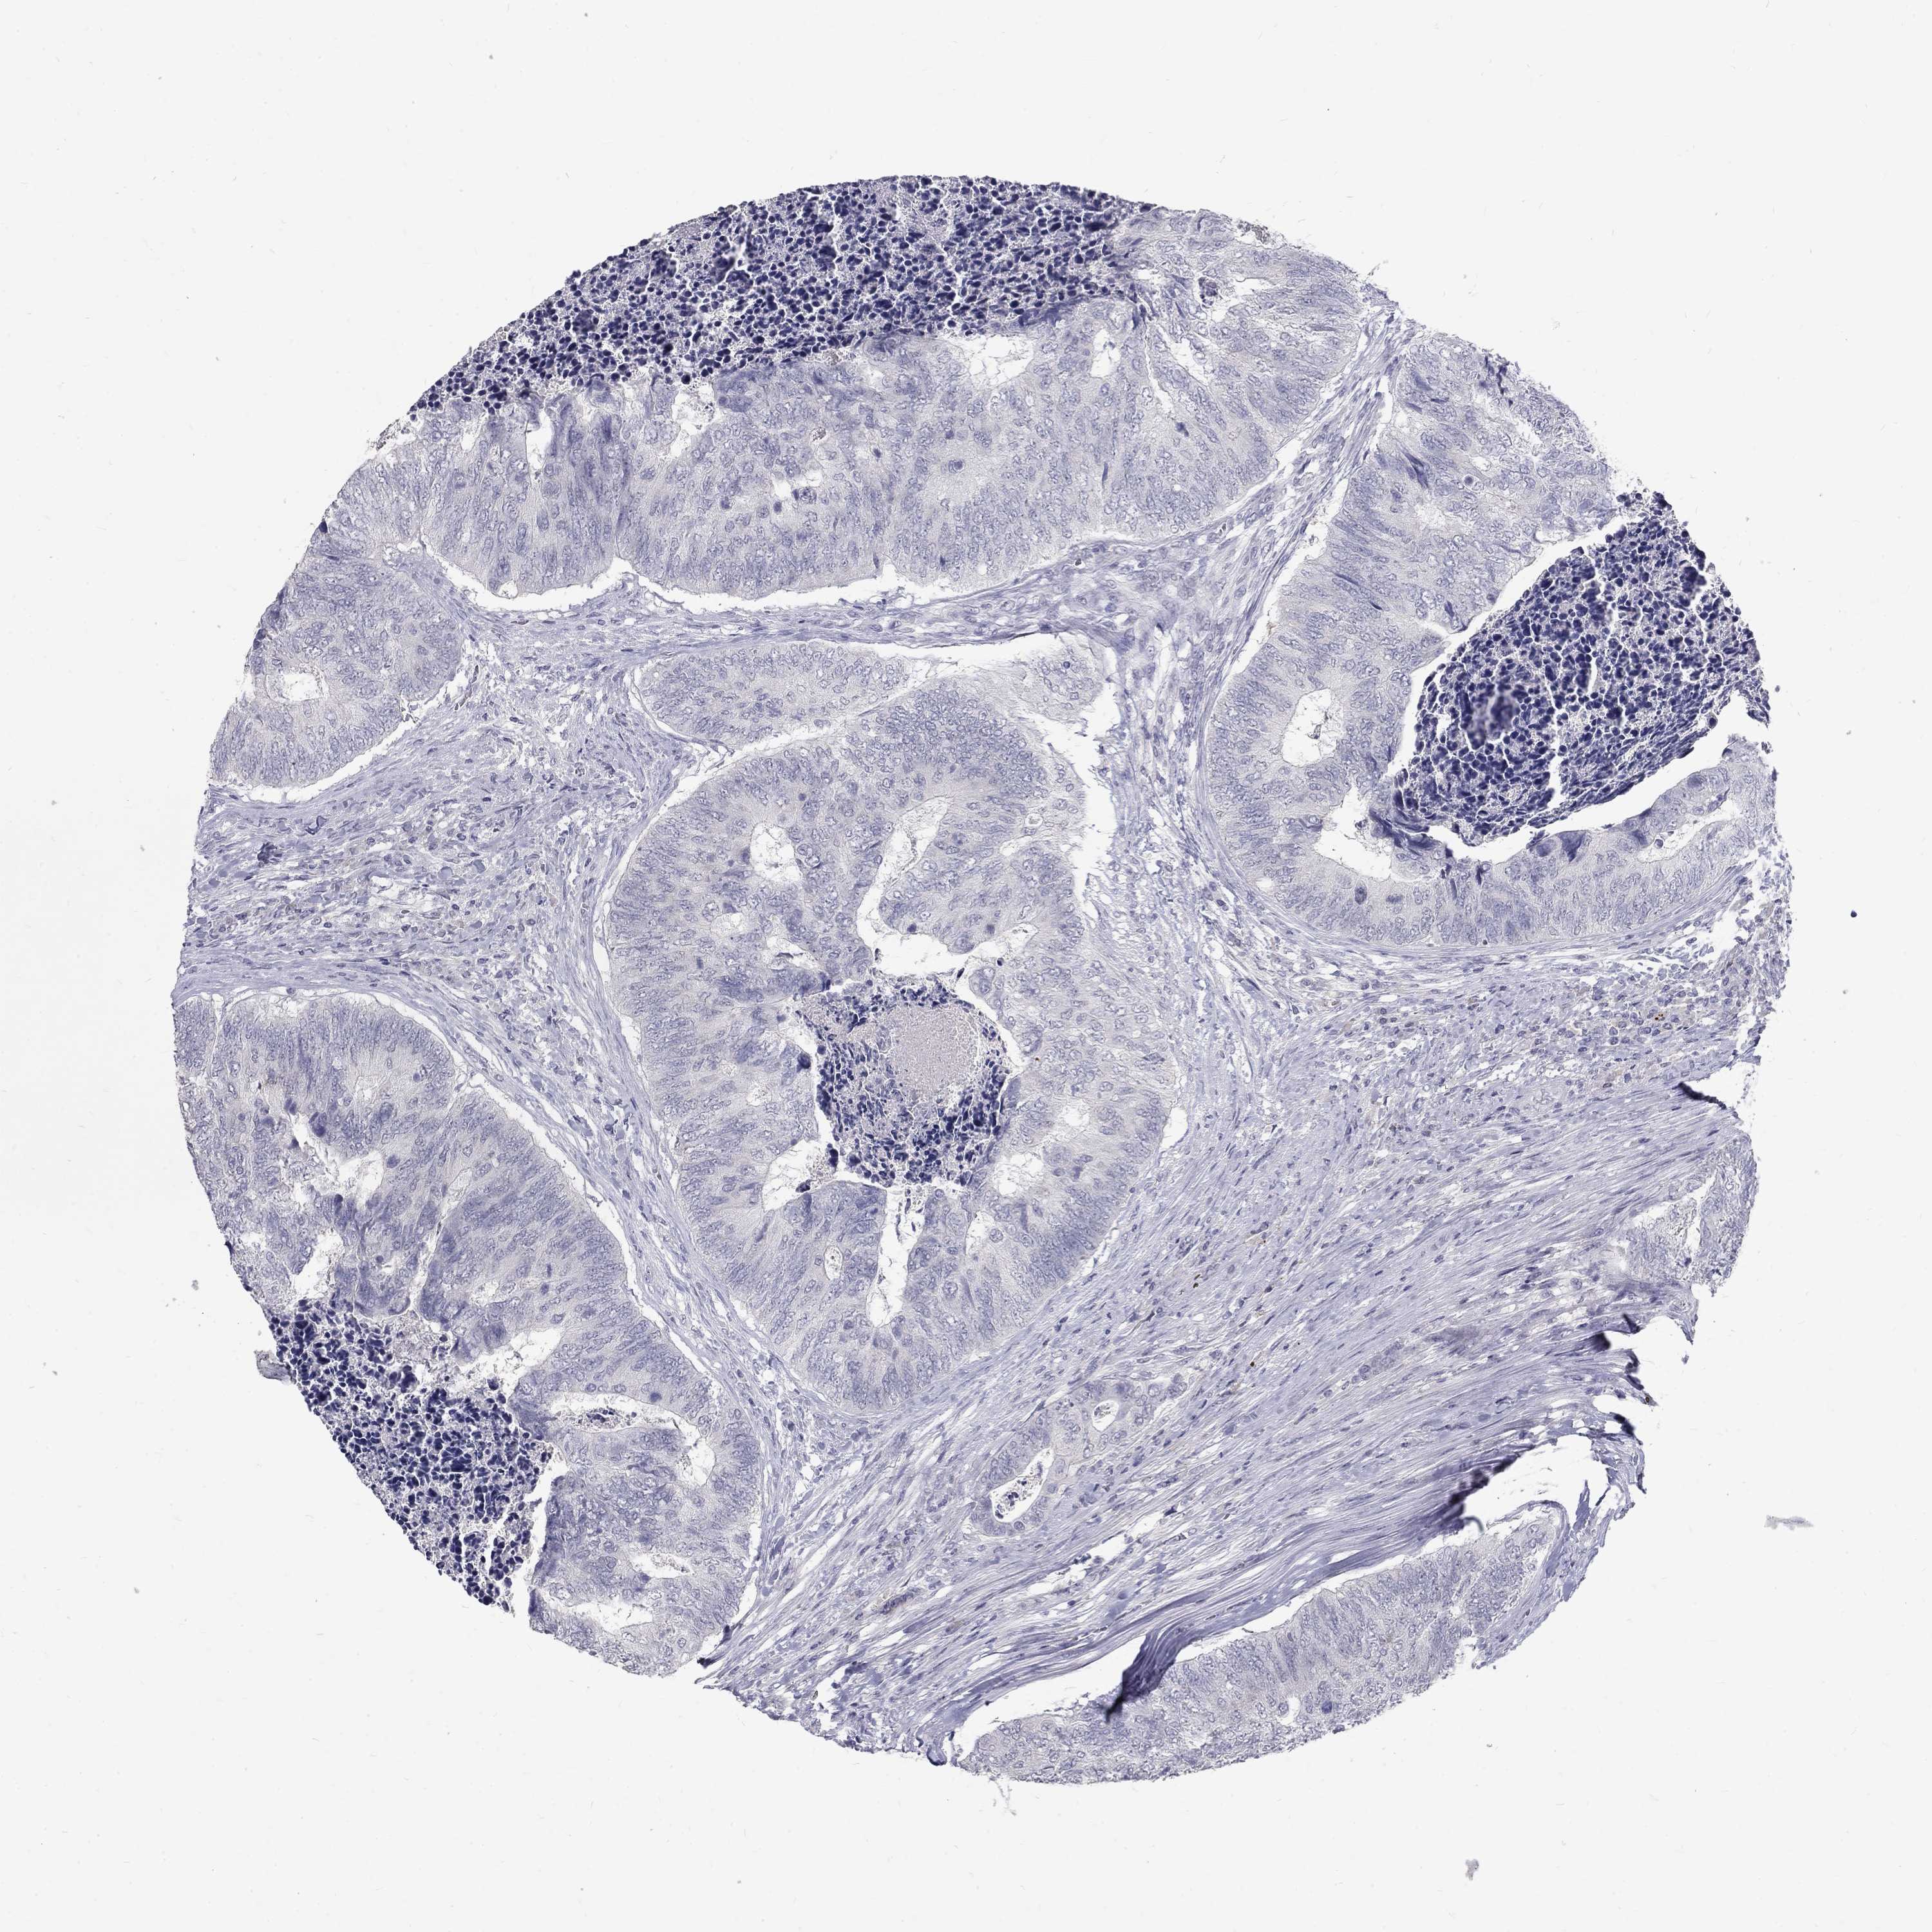

Colorectal cancer

Colon adenocarcinoma